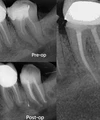

علاج الزرع السني